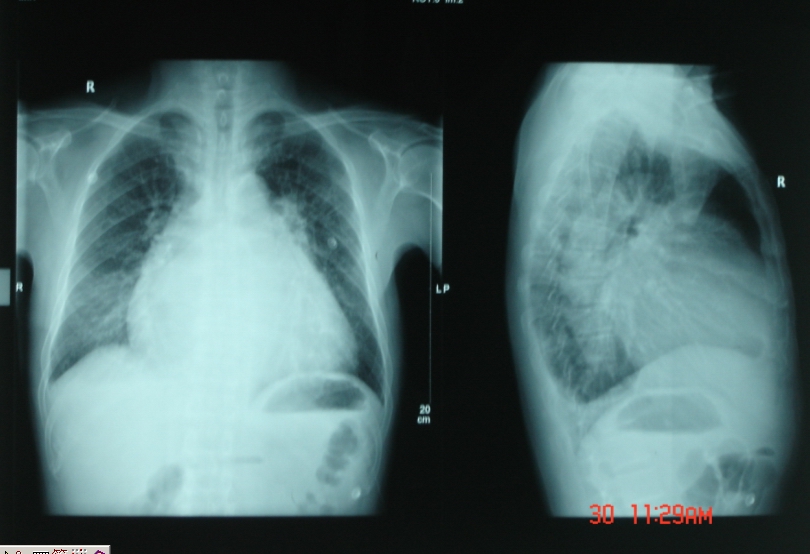

●胸片:

● 两肺纹理增多,增粗,呈“肺淤血”样改变,心影呈普大型,心胸比率约0.70,侧位片心前、后间隙变窄、消失,后肋膈角变钝。